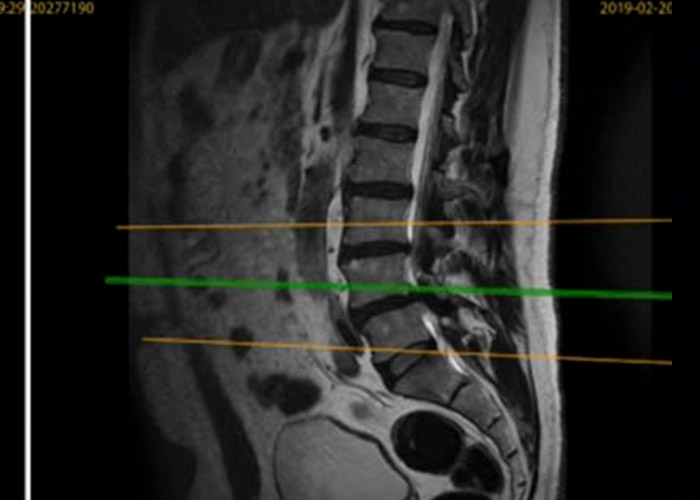

operacion-recidiva-hernia-discal-en-madrid

Operación

Con nuestra técnica ultra mínimanente invasiva, mediante incisión de 3mm le solucionamos el problema y el paciente no ha requerido fijación